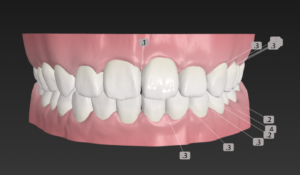

今回はインビザラインではなく

クリアコレクトを選択

治療はお口のスキャナー トリオスで

歯並びをスキャンから開始

🔶アフター🔶

正面